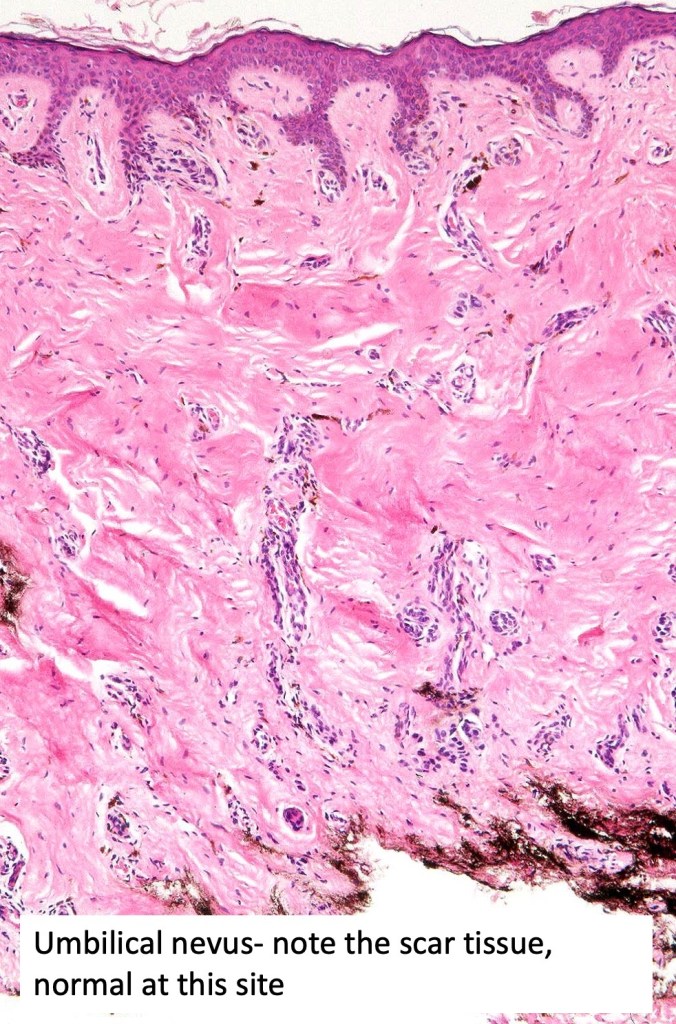

•Umbilical nevi can be confusing as scar tissue is to be expected

•Dermal fibrosis (sometimes lamellar)